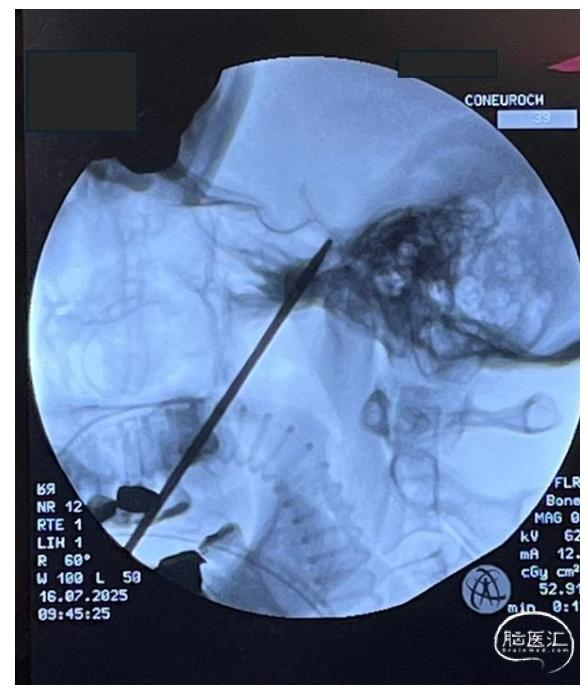

3.穿刺点定位与进针:采用电磁神经导航确认皮肤进针点与预设穿刺路径,同时以C臂透视实时确认穿刺针推进位置,并可通过造影剂验证球囊充盈是否到位。进针点通常位于患侧口角外侧约2.5 cm处(图2)。穿刺针初始推进时,将非优势手手指置入口腔,避免损伤口腔黏膜。所用穿刺针为KCA 11/15-10型穿刺针,配备双针芯、斜形与套管针针尖、11号球囊、球囊固定器、带旋塞的3 ml注射器及符合人体工学的侧翼。在透视引导下,沿瞳孔中线平面向岩骨嵴与斜坡交点推进穿刺针,侧位透视下以内耳道对齐确认方位(图3)。针尖触及骨质后,撤出针芯,将Axiem电磁传感器置入套管内,比对实际轨迹与术前导航预设路径的精准度(图4)。此阶段可出现反射性下颌抽搐,偶见脑脊液流出,无需特殊处理。

图3:术中侧位透视影像。